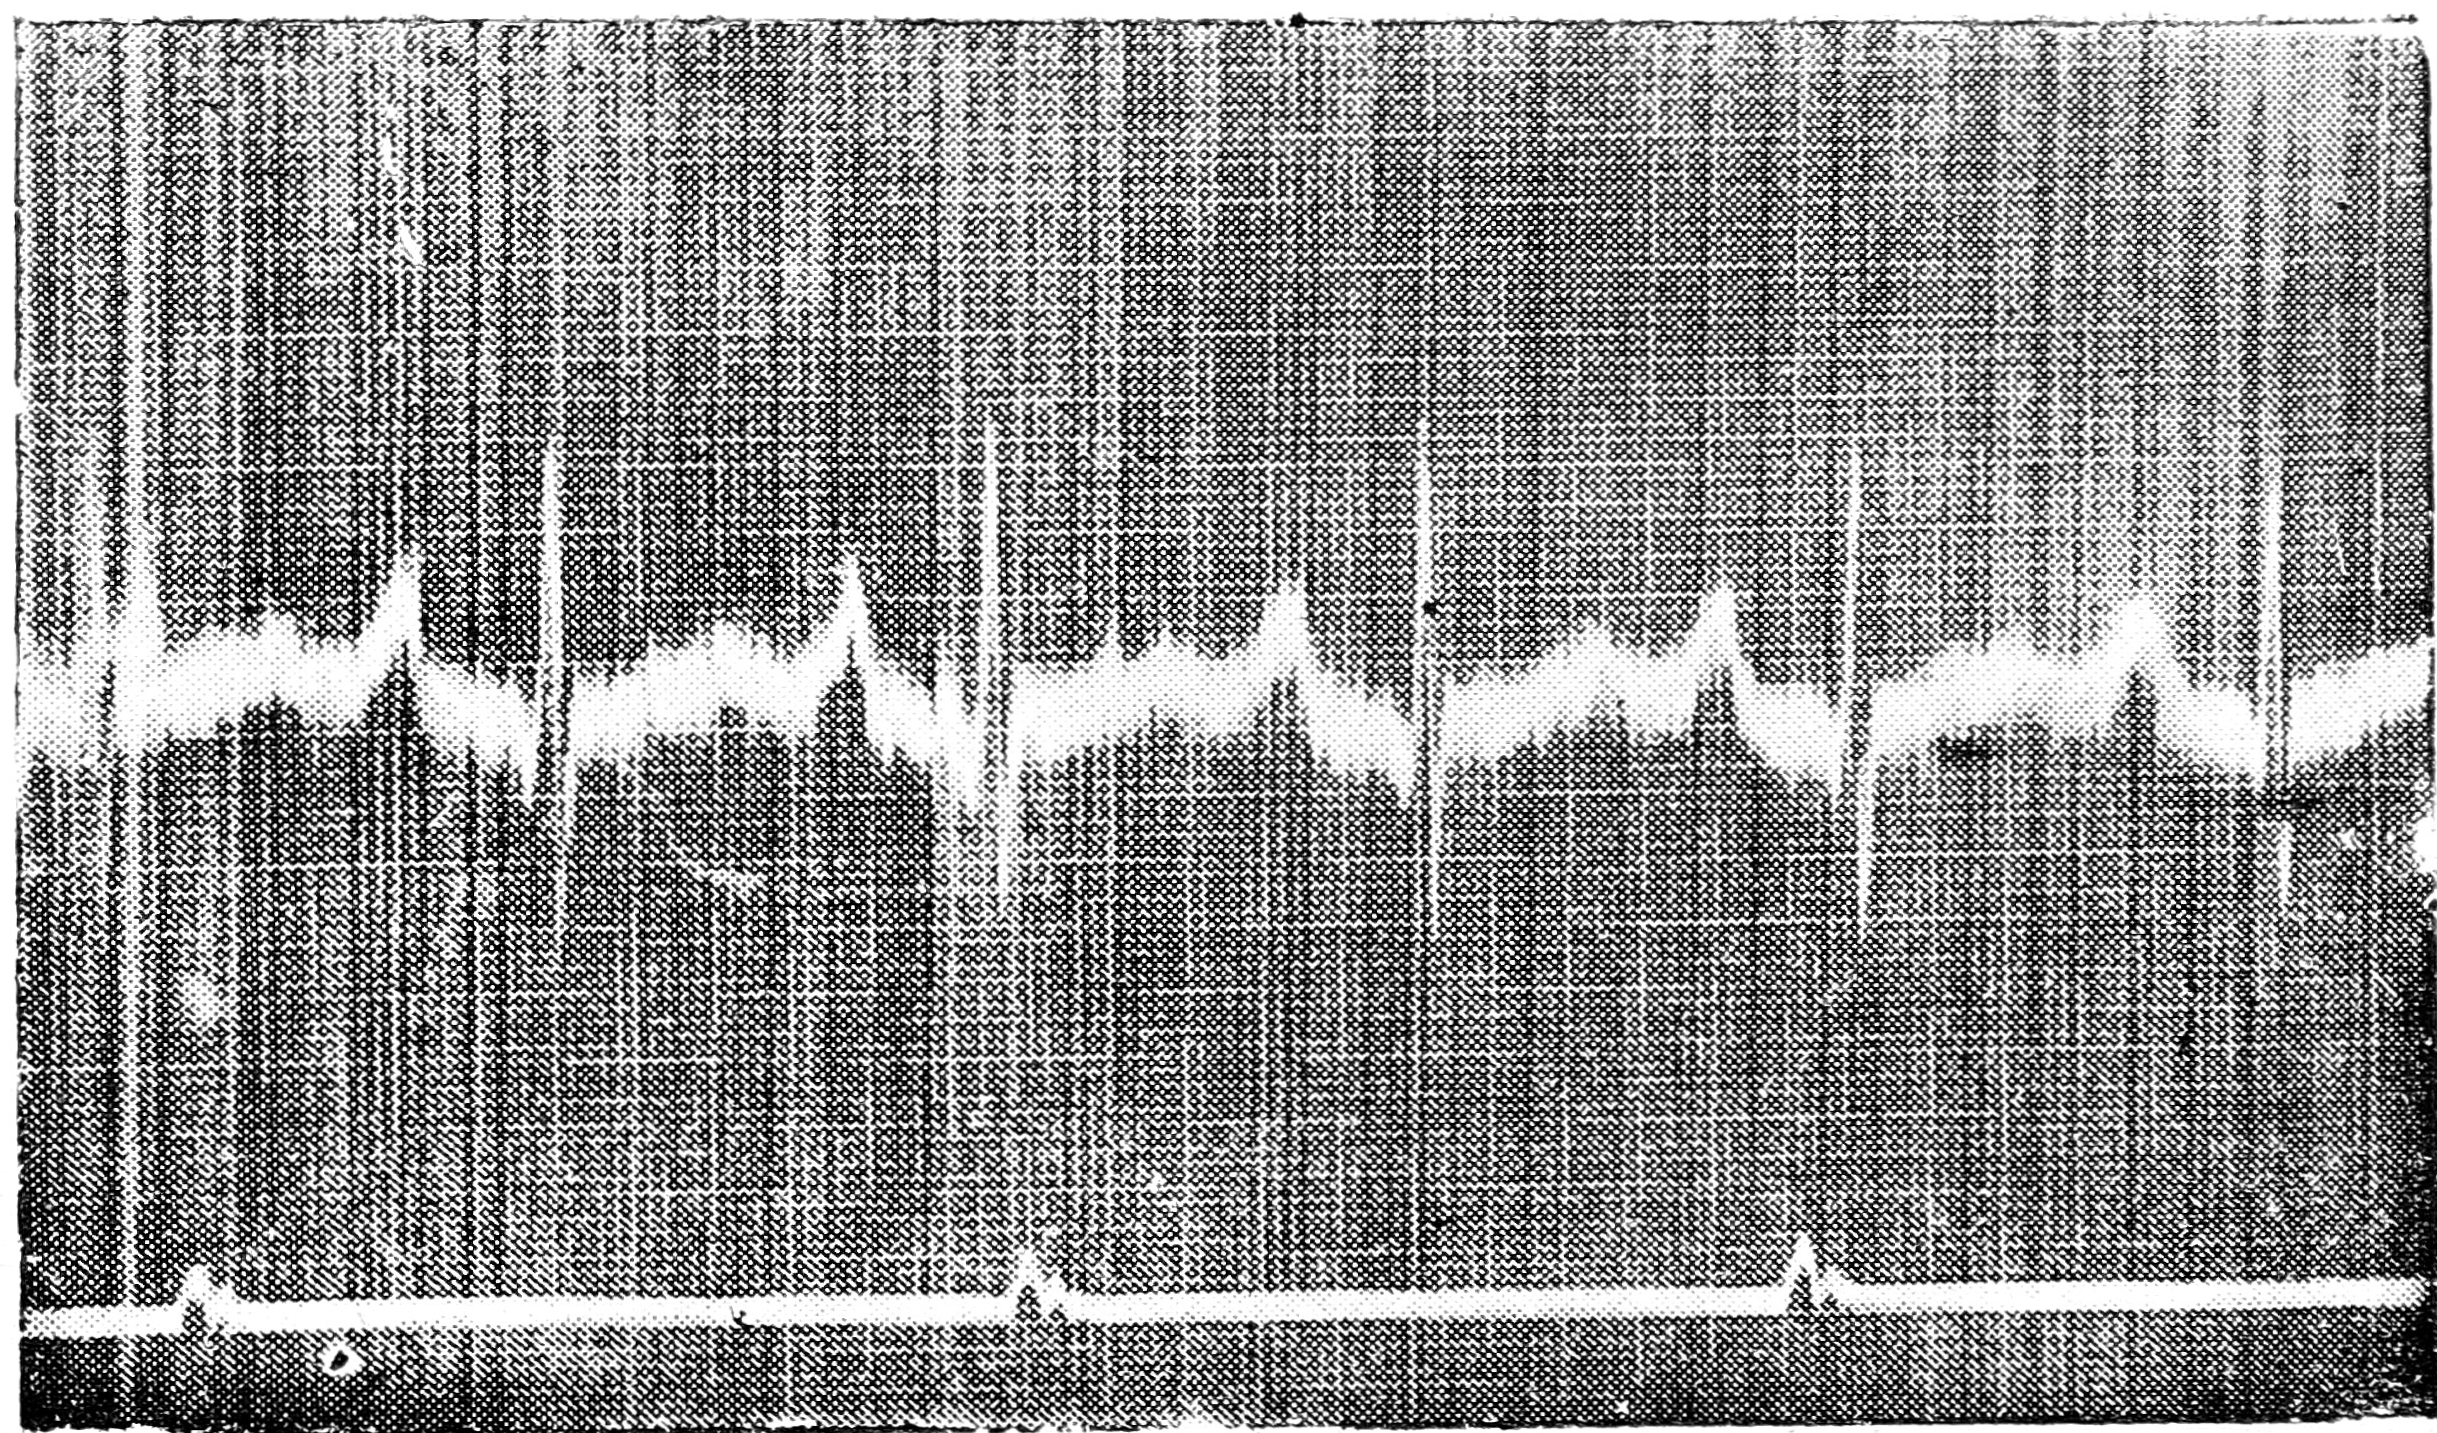

EKG №1. Фад-ва. I отвед. после бега на 5000 метр.

EKG № 2. Фад-ва. II отвед. после бега на 5000 метр.

EKG № 3. Фад-ва. III отвед. после бега на 5000 метр.

EKG № 4. Фад-ва. III отведение до бега. Рентгено-поперечное положение сердца.

EKG № 5. Иж-ого. I отвед. после бега на 5000 метр.

EKG № 6. Иж-ого. II отвед. после бега на 5000 метр.

EKG № 7. Иж-ого. III отвед. после бега на 5000 метр. Рентген до бега—расширение левого желудочка.

EKG № 8. Кад-ва. III отвед. после бега на 4000 метр.

EKG № 9. Фр-ва. III отвед. до бега.

EKG № 10. Фр-ва. III отвед. после бега на 1000 м. и на 800 метр.

EKG № 11. Ры-ва. III отвед. после бега на 1000 и на 800 метр.

EKG № 12. Шир-ва. III отвед. до бега.

Наиболее выраженные изменения Т. мы имеем у Фад-ва (см. EKG. за №№ 3, 4). В каждом желудочковом комплексе Т. имеет свое отличное от другого Т. изменение и направление, временами также двухфазность.

Анализ электрокардиограммы Фад-ва (см. EKG за №№1, 2,3,4) показывает нам, что наряду с расщеплением зубца R в III отведении мы имеем значительные изменения со стороны зубца Т., расширение и увеличение Р., неодинаковое время между желудочковыми комплексами с колебаниями от 0,58" до 0,66". Во II отведении мы видим, что зубец Р. в ряде комплексов превышает по высоте зубец Т., в других—зубцы Р. и Т. по высоте одинаковы и в третьих—зубец Р. ниже зубца T. В I отведении мы наблюдаем, что зубцы Р. в каждом комплексе отличаются друг от друга и они всегда ниже зубца Т.